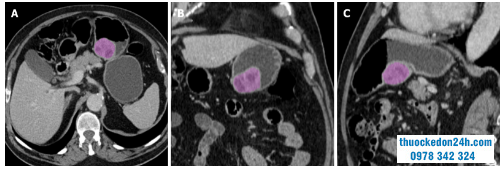

Việc phân đoạn có thể được thực hiện thủ công bởi các bác sĩ tạo hình dữ liệu hóa chuyên nghiệp, sử dụng phần mềm bán tự động hoặc tự động. Mặc dù việc phân đoạn bằng tay tốn nhiều thời gian và có thể thay đổi giữa các đầu đọc, nhưng nó vẫn được coi là tiêu chuẩn vàng cho hầu hết các nghiên cứu về tạo hình dữ liệu hóa. Việc phân đoạn thường được thực hiện bằng cách vẽ ROI trong biên khối u (Hình 1), tránh đưa vào bất kỳ mô ngoài dạ dày nào như niêm mạc ruột, thành phần trong ruột hoặc các mạch máu phúc mạc. ROI có thể được đặt trên một slide đơn (ROI 2D) mặt cắt ngang của khối u lớn nhất hoặc bao gồm toàn bộ tổn thương (3D ROI). Mặc dù sau này có thể nắm bắt được nhiều sự không đồng nhất của mô, nhưng lợi thế lâm sàng của nó vẫn còn được tranh luận.

Hình 1. Các ví dụ về phân đoạn tổn thương bằng phần mềm phân tích kết cấu